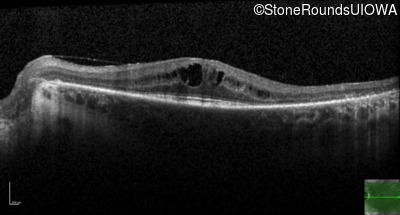

Age at visit: 49 years (Visit 2)